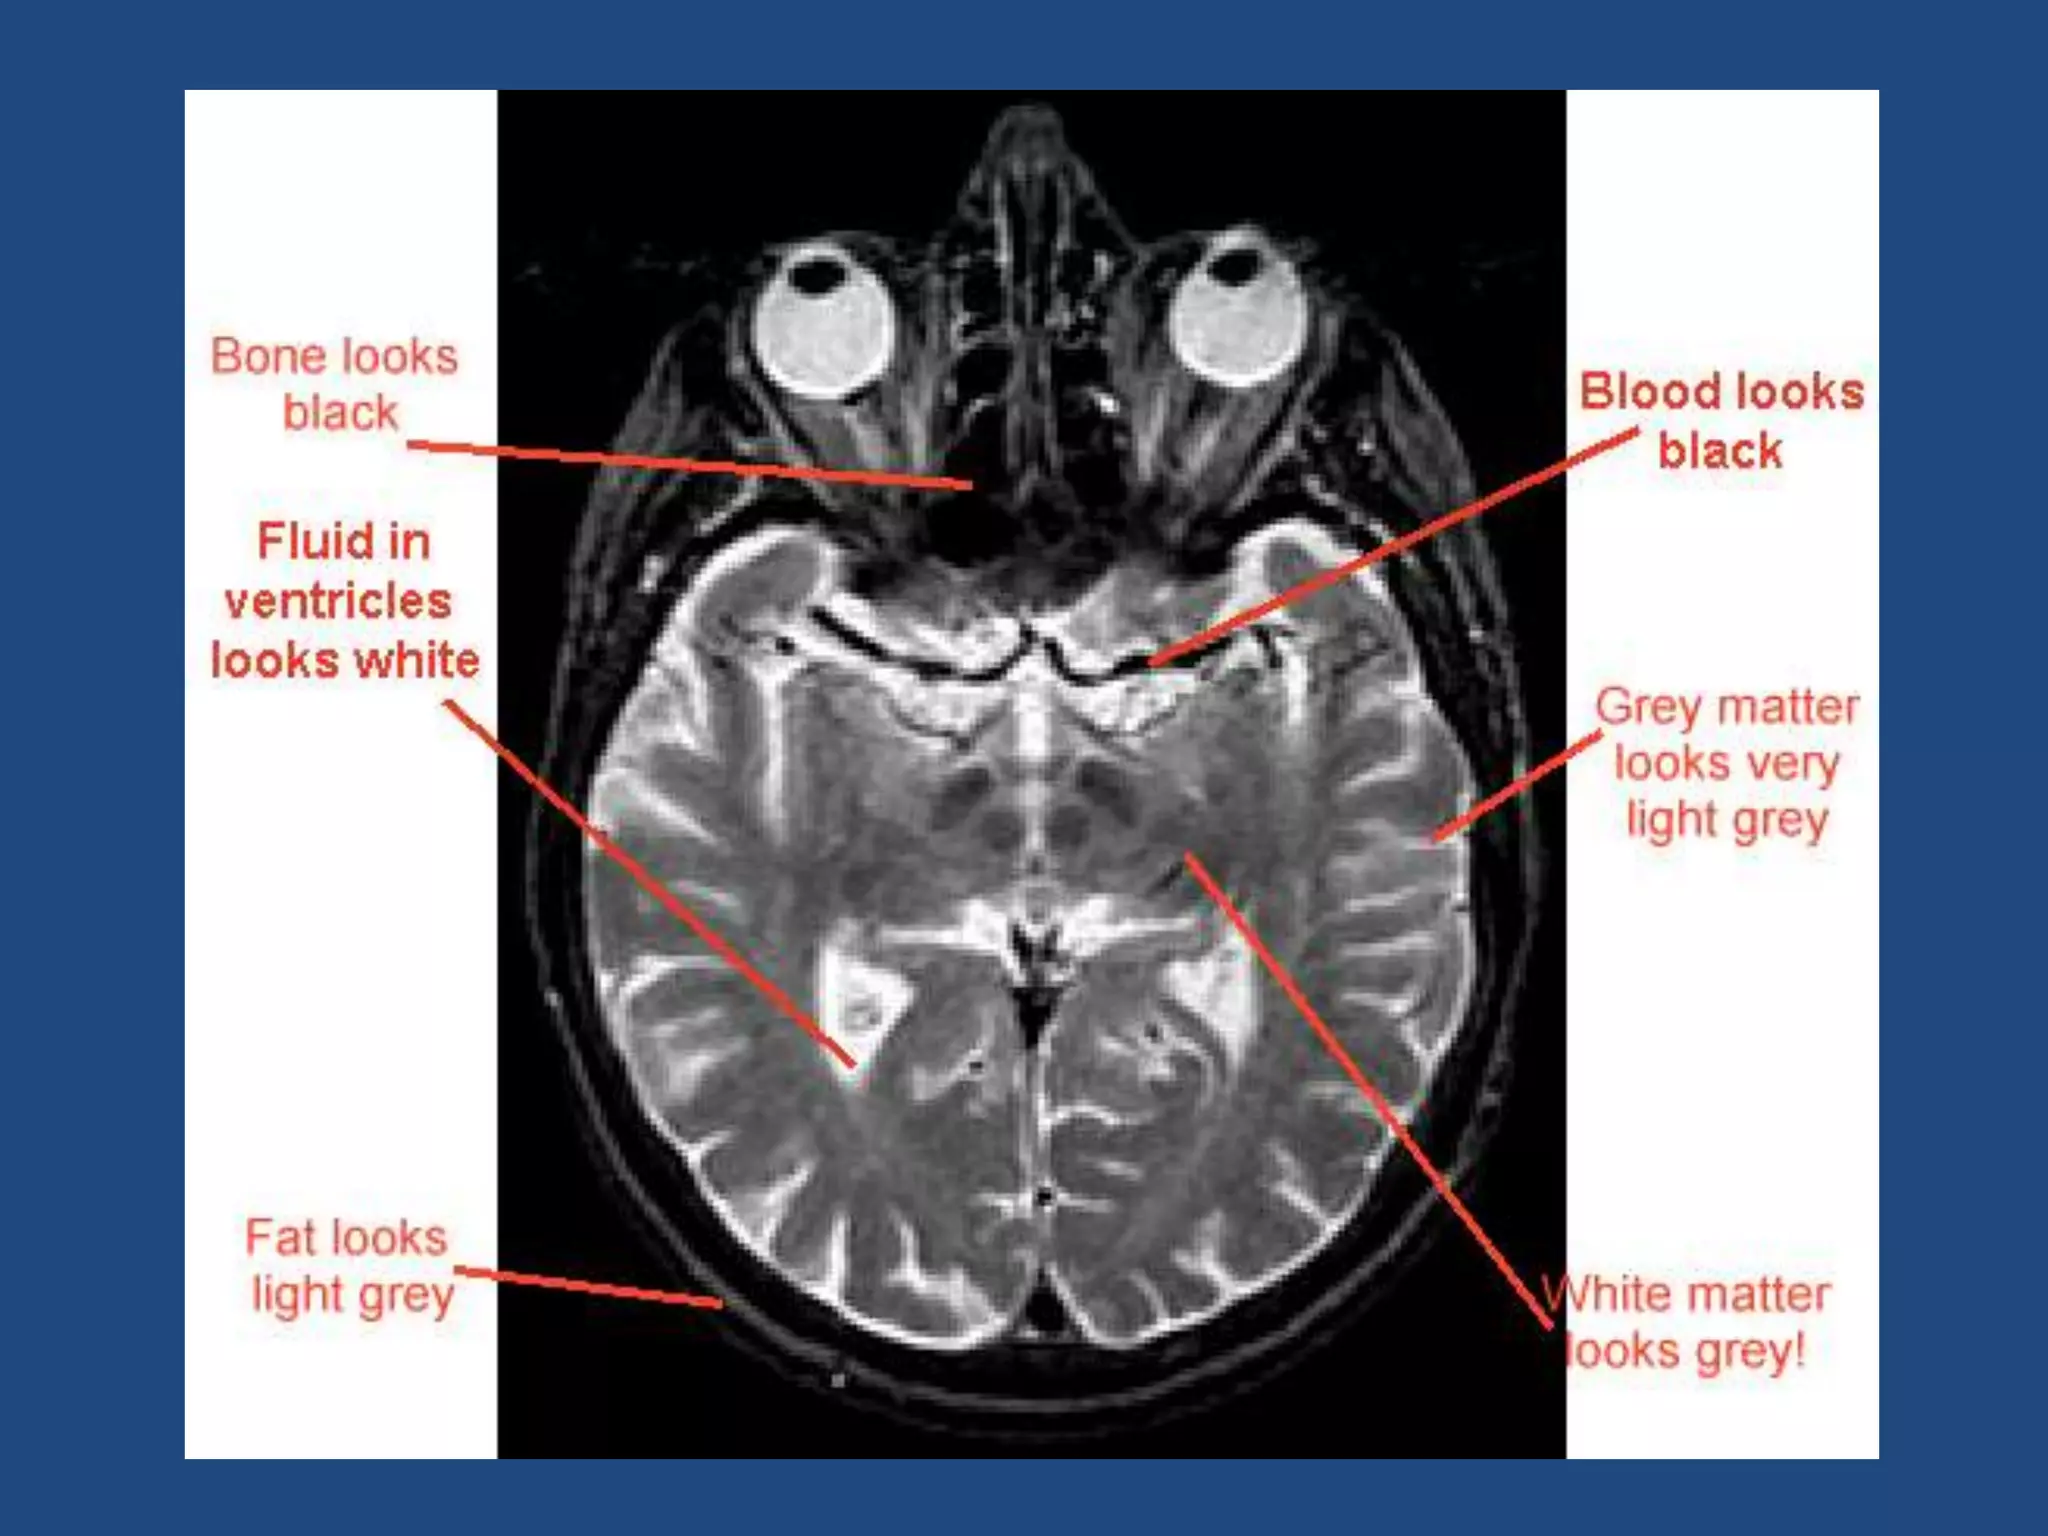

T1 time &T2 Decay are an intrinsic contrast parameter that are inherent to tissue being imaged. T1WI